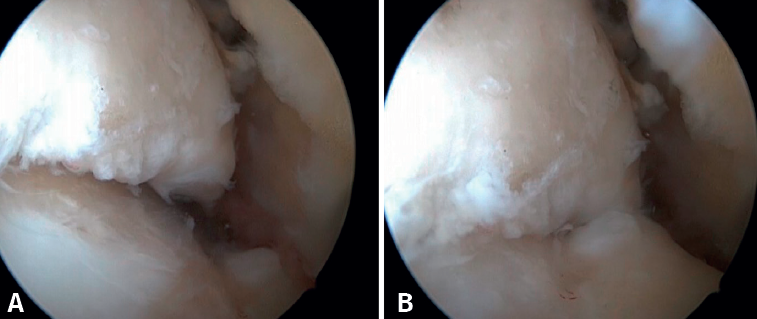

La confirmación del PAT se hará mediante visión directa durante la exploración artroscópica (Figura 4). Esta técnica permite visualizar toda la articulación, evaluar el estado del cartílago articular, los ligamentos, detectar la presencia de adherencias capsulares, sinovitis, engrosamiento sinovial, cuerpos libres, etc. Además, nos permitirá realizar test funcionales para poner de manifiesto posibles inestabilidades asociadas o valorar cómo se pinzan las partes blandas causantes de dolor. La presencia de lesiones del LTFA es, en nuestra experiencia, muy frecuente.

Figura 4. Pinzamiento anterolateral de partes blandas en un paciente con lesión concomitante del ligamento talofibular anterior, al que se le hizo una reparación artroscópica asociada a la resección del pinzamiento.